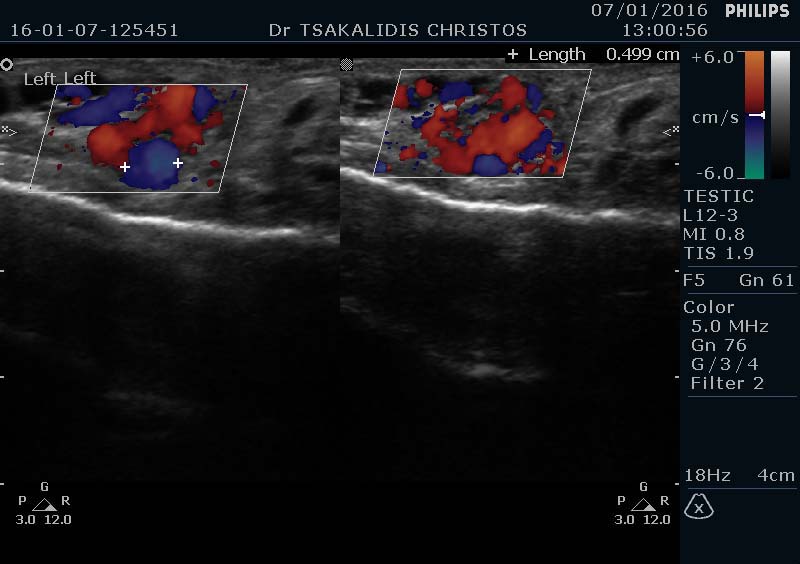

Κιρσοκήλη ονομάζεται η διεύρυνση των φλεβών πάνω από τους όρχεις. Παρατηρείται συνήθως διόγκωση του όσχεου στην περιοχή αυτή, όταν πρόκειται για μεγάλη-κλινική κιρσοκήλη είναι ορατή με τα μάτια ή με την ψηλάφηση από τον ουρολόγο. Η τεκμηρίωση όμως της διάγνωσης γίνεται με το έγχρωμο υπερηχογράφημα TRIPLEX όσχεου. Παρατηρείται περισσότερο στον αριστερό όρχι, αλλά μπορεί να υπάρχει και αμφοτερόπλευρα. Παρατηρείται περίπου στο 1/3 των ανδρών. Είναι μια από τις πιο συχνές αιτίες υπογονιμότητας στον άνδρα. Μπορεί να επηρεάσει μια ή όλες τις παραμέτρους του σπερμοδιαγράμματος, τον αριθμό, την κινητικότητα και τη μορφολογία των σπερματοζωαρίων, αλλά αυξάνει και το ποσοστό των βλαβών στο DNA αυτών.

υπερηχογράφημα TRIPLEX όσχεου